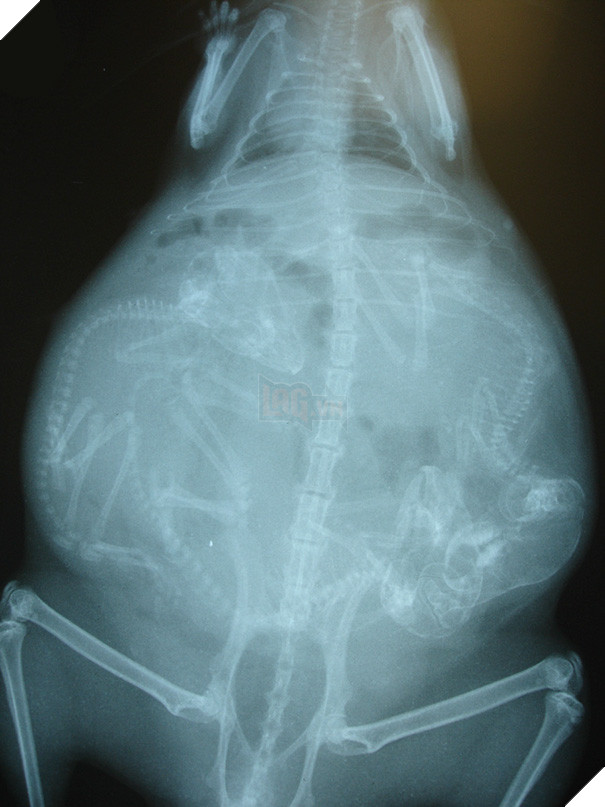

Một bà mẹ mèo đang mang thai. Thời gian thai kỳ của mèo khoảng 56 - 71 ngày, trung bình kéo dài khoảng 67 ngày và chúng có thể "sản xuất" 3 - 4 lứa mỗi năm.